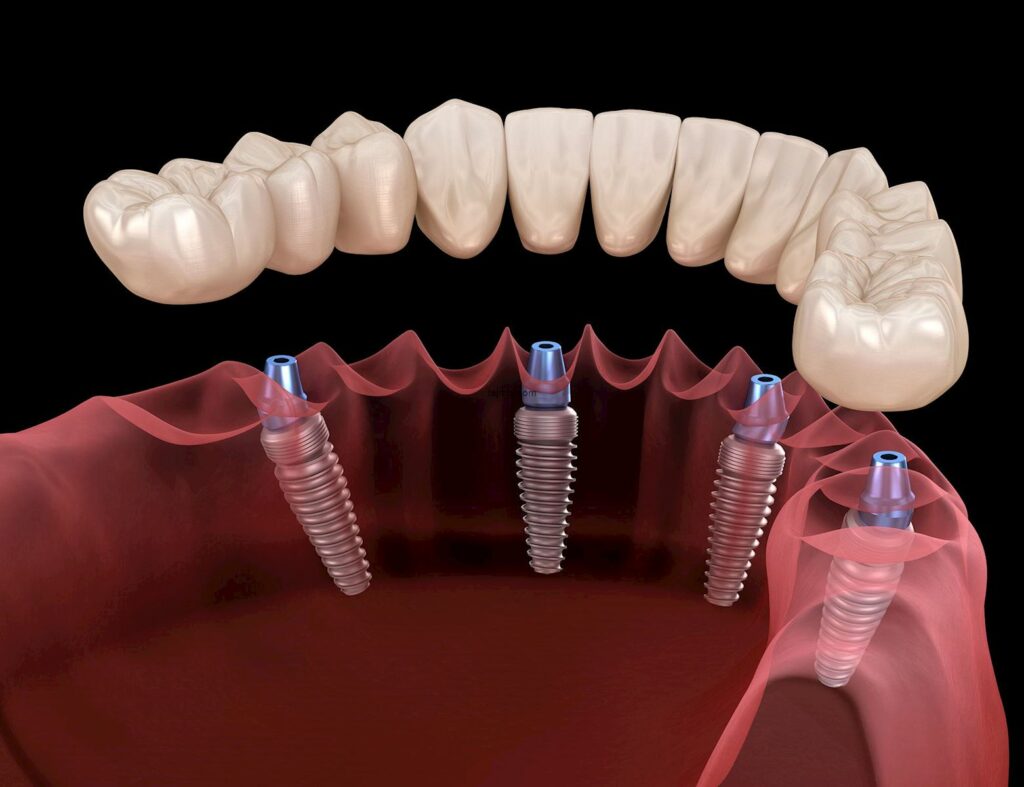

تهدف زراعة الاسنان الى تعويض الأسنان المفقودة بعد خلعها ب زرعات مصنوعة من مواد متوافقة حيوياً توضع في العظم لتعويض الأسنان المفقودة

2. البدء بعملية زرع الأسنان يتم غرس الزرعة في مكان السن المفقود، إذ تعمل الزرعة كقاعدة متينة لتثبيت السن الجديد .

3. بعد أن تلتئم منطقة الزراعة بشكل كامل، يتم عمل شق آخر، ويتم شد الدعامة وتثبيتها في منتصف الزراعة

٤.بعد هذا الإجراء، تترك المنطقة للإستشفاء التام لبضعة أيام، وستكون الدعامة بارزة قليلا فوق اللثة. ويمكن وضع تاج مؤقت فوق الدعامة أو استخدام طقم الأسنان فوقها أثناء فترة التعافي من مرحلة الثانية.

٥. المرحلة الأخير من زراعة الأسنان، وهو وضع التاج على الدعامة. حيث يقوم الطبيب بأخذ فكرة عن شكل الأسنان المحيطة، ليصنع تاجاً يتناسب مع أشكال الأسنان الموجودة وذلك في فترة الاستشفاء خلال المرحلتين السابقتين.الطبيب سوف يقوم بمطابقة لون التاج قدر الإمكان مع لون الأسنان الطبيعية، ليعطيه إبتسامة يظهر فيها تناسق في اللون بشكل موحد. ثم يتم تثبيت التاج على الدعامة ليكتمل إجراء الزراعة.

يمكن استخدام زراعة الأسنان لاستبدال سن واحد أو عدة أسنان أو كل الأسنان. الهدف من استبدال الأسنان في طب الأسنان هو استعادة الوظيفة وكذلك الجماليات. تعتبر زراعة الأسنان متحفظة حيث يمكن استبدال الأسنان المفقودة دون التأثير على الأسنان المجاورة أو تغييرها. علاوة على ذلك، نظرًا لأن زراعة الأسنان تندمج في بنية العظام، فهي مستقرة جدًا ويمكن أن يكون لها شكل وملمس الأسنان الطبيعية.